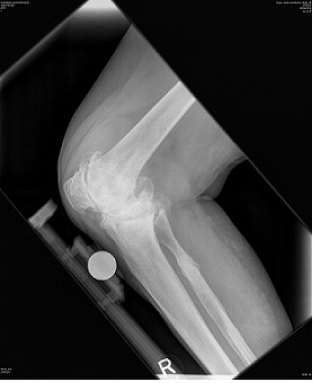

A 76 year old woman presented with a painful, valgus right knee which had progressively worsened over past 2 years. On clinical examination she had a marked valgus deformity of her right knee measuring 49° using a goniometer. Range of motion on examination was measured to be 5° to 100° with an extensor lag of 15°; the valgus deformity was not correctable on clinical examination. Radiographs confirmed a massive valgus deformity of the right knee with a bony defect in the lateral femoral condyle and lateral tibial plateau (Figure 1–3). The patient was consented to have a simultaneous peri-articular femoral osteotomy and total knee arthroplasty procedure in order to address the severe valgus deformity and osteoarthritis. The patient was informed that the data concerning her case would be submitted for publication and an informed consent obtained. Pre and post operative WOMAC and VAS scores were obtained.

Figure 1 Preoperative AP view of the knee.

Figure 2 Preoperative lateral view of the knee.